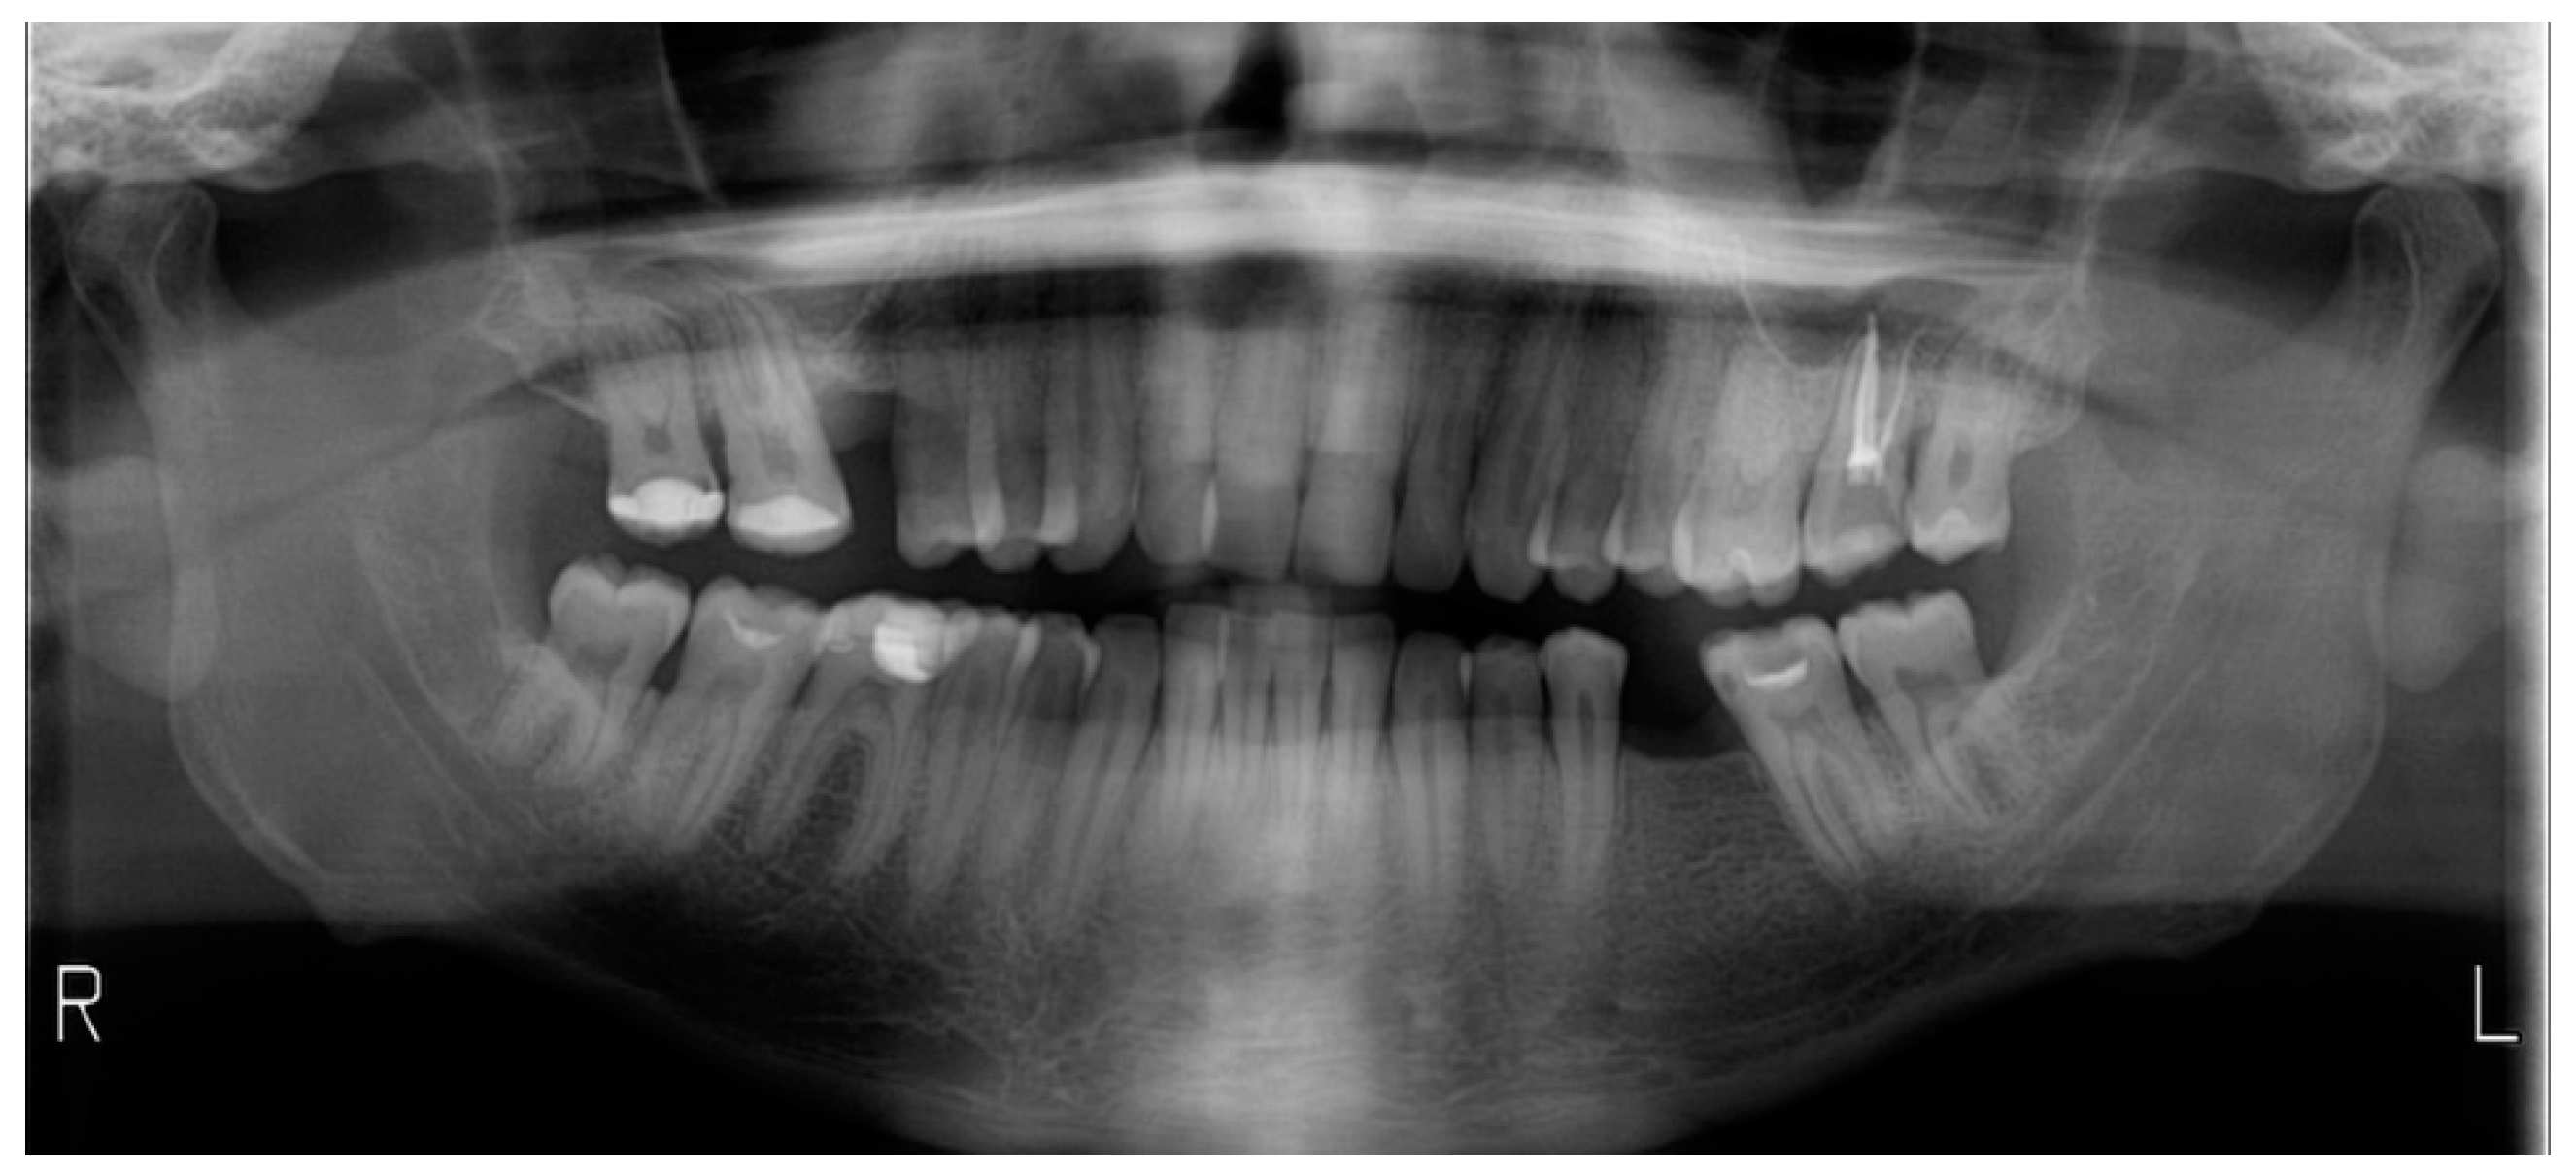

2.3.1. Example—Anterior Open-bite

2.3.2. Example 2—Extraction Space Closure